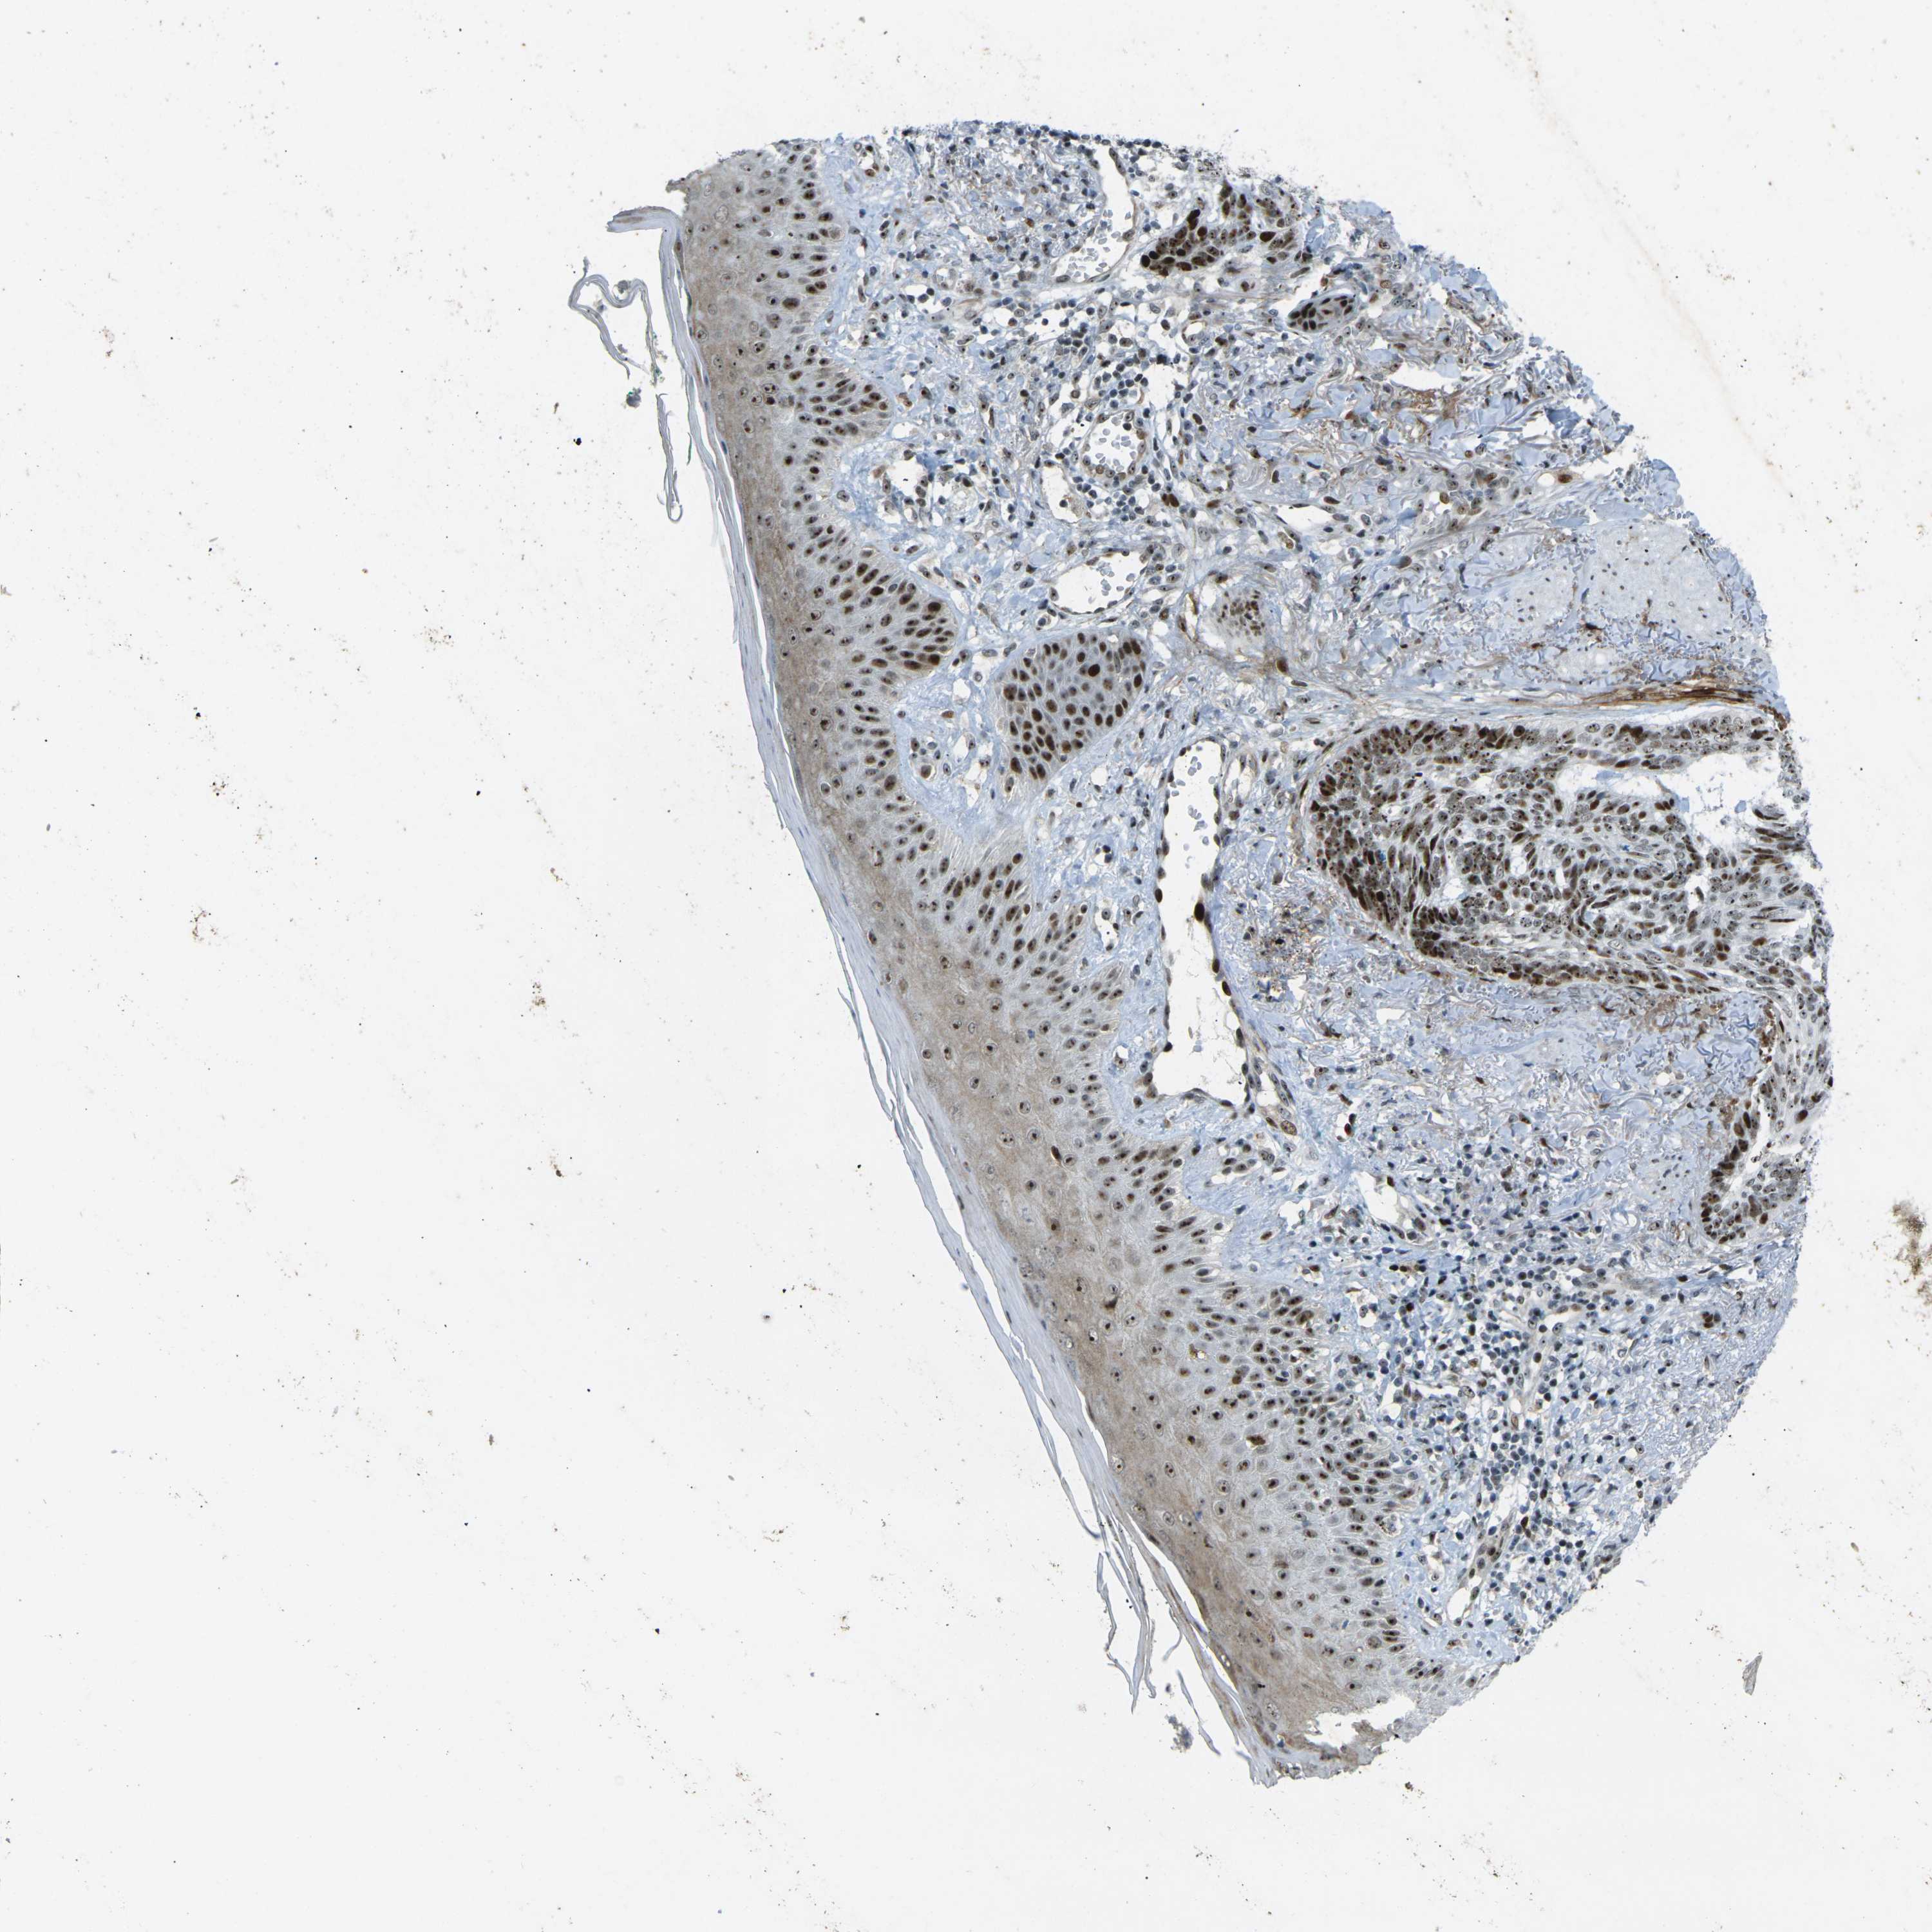

SKIN CANCER - Protein expressioni

A mouse-over function shows sample information and annotation data. Click on an image to view it in a full screen mode. Samples can be filtered based on level of antibody staining by selecting one or several of the following categories: high, medium, low and not detected. The assay and annotation is described here.

Each image is clickable and will lead to virtual microscopy that enables deeper exploration of all samples and also displays staining intensity scores, fraction scores and subcellular localization as well as patient and tissue information for each sample.

Antibody HPA054975

Antibody CAB011464

Antibody CAB035990

Antibody CAB080407

Staining

High

Medium

Low

Not detected

Intensity

Strong

Moderate

Weak

Negative

Quantity

>75%

75%-25%

<25%

None

Location

Nuclear

Cytoplasmic/membranous

Cytoplasmic/membranous,nuclear

Squamous cell carcinoma, NOS

Squamous cell carcinoma, metastatic, NOS